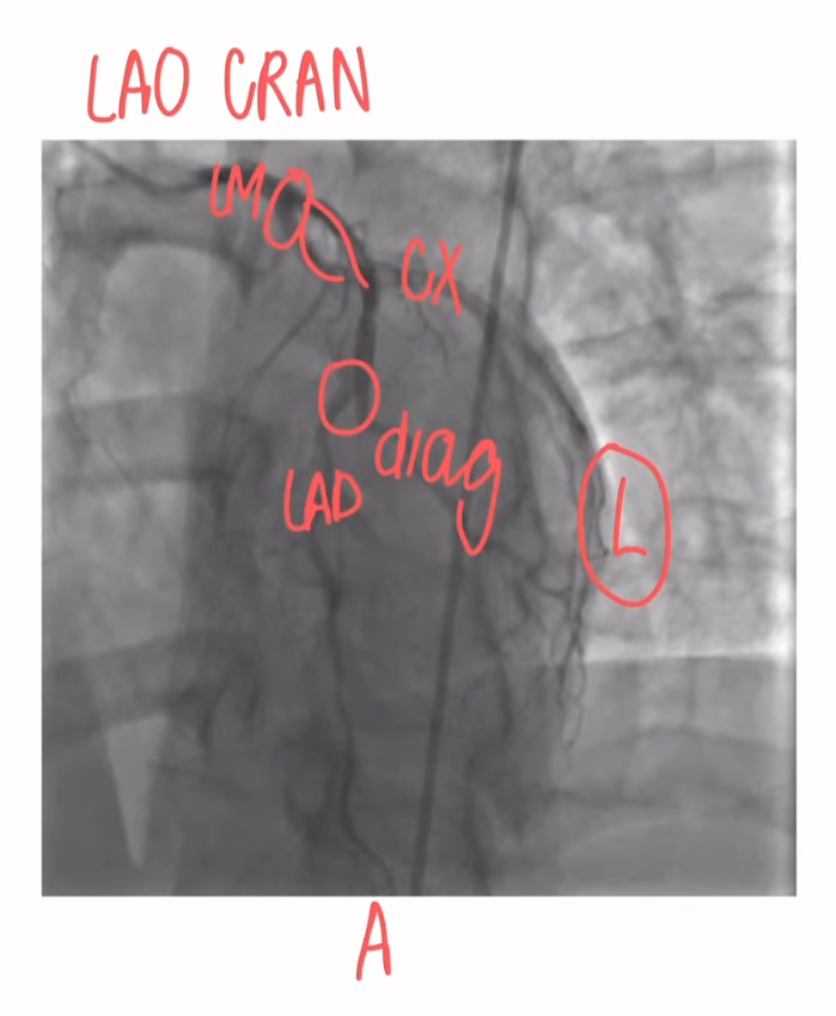

LAO Cranial